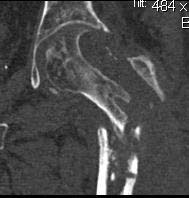

If there is no osteomyelitis, I would recommend open insertion of Gamma Nail

and Bone Grafting.

кт